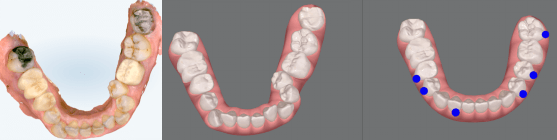

当院では、体の歪みを調べ、その方にとって無理のない安定した顎位を見つけ出し、その位置で噛み合わせを構築することを重要視した矯正治療を行っています。

また、歯列矯正だけではなく、全顎的に歯の治療(補綴治療)を必要とする方も体の歪みをみる上で治療をすることがとても重要です。